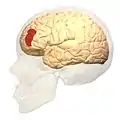

Brodmann area 46

Brodmann area 46, or BA46, is part of the frontal cortex in the human brain. It is between BA10 and BA45.

BA46 is known as middle frontal area 46. In the human brain it occupies approximately the middle third of the middle frontal gyrus and the most rostral portion of the inferior frontal gyrus. Brodmann area 46 roughly corresponds with the dorsolateral prefrontal cortex (DLPFC), although the borders of area 46 are based on cytoarchitecture rather than function. The DLPFC also encompasses part of granular frontal area 9, directly adjacent on the dorsal surface of the cortex.

Frontal view.